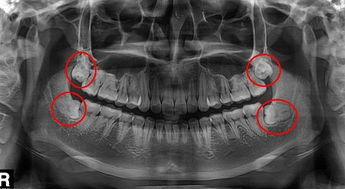

很多人都是在做完口腔檢查後才知道有4顆智齒,原來自己懵懂的以為(wei) 隻有一顆疼痛,是不是隻有一兩(liang) 顆,因為(wei) 受盡了智齒發炎引起的疼痛,所以想要一次性全部拔除,以絕後患,但是醫生告知,一般智齒拔牙是不建議一次性拔除4顆的。...

很多人都是在做完口腔檢查後才知道有4顆智齒,原來自己懵懂的以為(wei) 隻有一顆疼痛,是不是隻有一兩(liang) 顆,因為(wei) 受盡了智齒發炎引起的疼痛,所以想要一次性全部拔除,以絕後患,但是醫生告知,一般智齒拔牙是不建議一次性拔除4顆的。

通常智齒拔牙是建議一次性拔除一顆的,如果是身體(ti) 條件比較好的**,耐受力也比較好的,可以根據實際情況一次性拔除同側(ce) 的上下牙。但是可能也有例外,根據很多國外的朋友描述,在國外拔牙如果要求4顆一起拔除是可以的,而且采用全麻拔牙就可以,但是價(jia) 格是相當的貴,雖然有4顆牙齒一次性拔除的勇士,但是不建議大家效仿,畢竟每個(ge) 人的身體(ti) 情況和耐受程度是不同的。

而且是否4顆智齒都需要拔除,可以先到醫院檢查智齒的情況,如果是有牙齒缺失的情況,但是想要做正畸矯正整齊牙齒的,可以先確定智齒是否可以利用起來,如果可以利用,是不需要進行拔除的,如果不能利用,正畸也需要拔除智齒的話,建議還是盡早拔除比較好。一般如果有想要正畸的**,建議提前告知醫生你的需求,便於(yu) 醫生為(wei) 你判斷一下是否需要拔除智齒。

深圳牙科醫院醫生表示,智齒不需要一次性全部拔除,分幾次進行拔除痛苦更小一些,因為(wei) 智齒拔除難度比較大,拔牙後一兩(liang) 天會(hui) 有嚴(yan) 重的疼痛和臉部對應位置的腫脹,如果是同側(ce) 兩(liang) 顆牙齒或者是單顆智齒拔除,不會(hui) 影響另一側(ce) 咀嚼和進食,所以這是比較好的。建議大家可以采用這樣的方式。